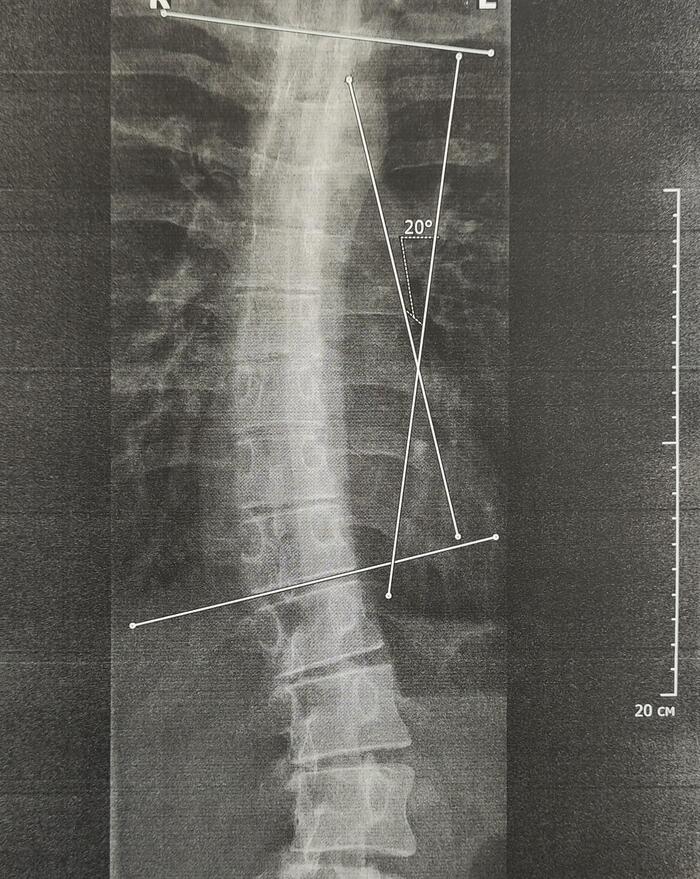

На Р-граммах грудного, поясничного отделов позвоночника определяется S -образное искривление оси позвоночника, с левосторонней дугой, вершиной на Th10,угол девиации 20 град., правосторонней дугой, вершиной на L2, углом девиации 15 град.

Итоговый диагноз: Патологический гиперкифоз грудного отдела позвоночника 4 ст. по Коббу. Клиновидная деформация тел Th6, Th7, Th8 позвонков, как следствие перенесенной остеохондропатии, соответствует болезни Шейермана-Мау.S-образный сколиоз 2ст.Остеохондроз грудного, поясничного отделов позвоночника.

В данном случае непризывные категории годности будут по сколиозу 2 ст(угол искривления более 18 град.)-ст.66в-В(ограниченно годен к в/сл), гиперкифозу грудного отдела позвоночника 4 ст, с клиновидной деформацией 3х позвонков грудного отдела как следствие остеохондропатии-ст.66а-Д(не годен к в/сл),иногда ставится 66в-В.